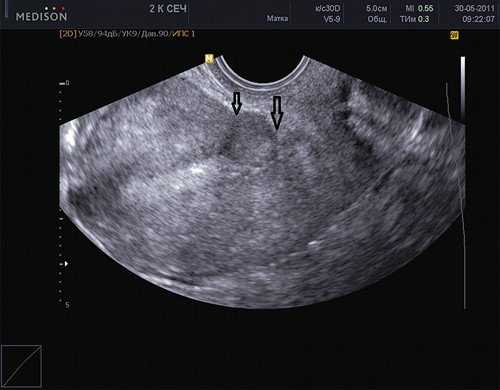

- два и более КС в анамнезе, которые способствуют увеличению поверхности рубцовой ткани (рис. 2);

Рис. 2. Два рубца на матке. Стрелками помечены два рубца после двух кесаревых сечений.